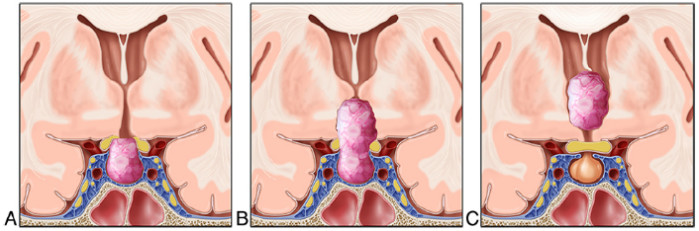

DOI: https://doi.org/10.3171/2018.5.JNS18198

第三脑室内颅咽管瘤(IVCs)已被业内认为是所有颅咽管瘤(CPAs)中“构成最大的手术挑战”的一类。各种开放性显微外科手术方法已被用于切除这类肿瘤。尽管近年来越来越多的专家会使用鼻内镜入路(EEA)的方法,但许多研究人员仍然建议不使用EEA的方法来切除IVCs。本文作者报道了迄今为止最大数量的利用EEA去切除IVCs。

研究人员回顾了过去14年前瞻性地的手术病例,在纽约长老会医院与威尔康奈尔医学院中通过EEA切除IVCs的数据。术前检查MRI的结果被两名独立神经外科医生和一名神经放射学家用于鉴定IVCs。而患者的术前和术后的内分泌、眼科或放射学以及其他相关疾病情况,则通过回顾性的图表和容量放射学分析来确定。

在2006年1月至2017年8月期间,共10名患者(4名男性,6名女性),年龄从26岁到67岁不等,接受了利用EEA方式的IVCs切除术。术前内分泌障碍患者占70%,而视力下降患者占60%。在该10例患者中,有9例(90%)实现了全切除,其余患者实现了近全切(98%),30%的患者病理为鳞状乳头型。有采用封口“密封垫”技术,利用鼻中隔皮瓣覆盖并进行腰大池引流(9例)或脑室引流(1例)。术后患者,分别有90%和70%的患者存在完全的垂体前叶和垂体后叶功能不全。此外,有4例患者的术前视力正常,3例术后视力稳定。另外,其中一位病人在术后发现了不协调的眼斜视。在6例视力低下的患者中,2例术后视力稳定。其余4例患者肿瘤切除后视力均有明显改善,1例患者视力完全恢复正常。除了上述的一病例(10%)外,没有术后神经功能下降的病例。而1例病态肥胖患者术后发生脑脊液漏的情况,需要再次手术进行修补。在平均随访46.8个月(4-131月)后,2例患者(20%)出现肿瘤复发,1例接受放疗,1例接受化疗。而这两名患者都是第三脑室内颅咽管瘤全切者。

本研究报告中描述的10例患者是迄今为止使用EEA进行切除治疗的最多的IVC患者。EEA切除第三脑室内颅咽管瘤属于一种安全有效的手术方式,应被认为是治疗这类具有挑战性的肿瘤的一种较优的手术方式。

图:IVCs切除的手术步骤示意图。